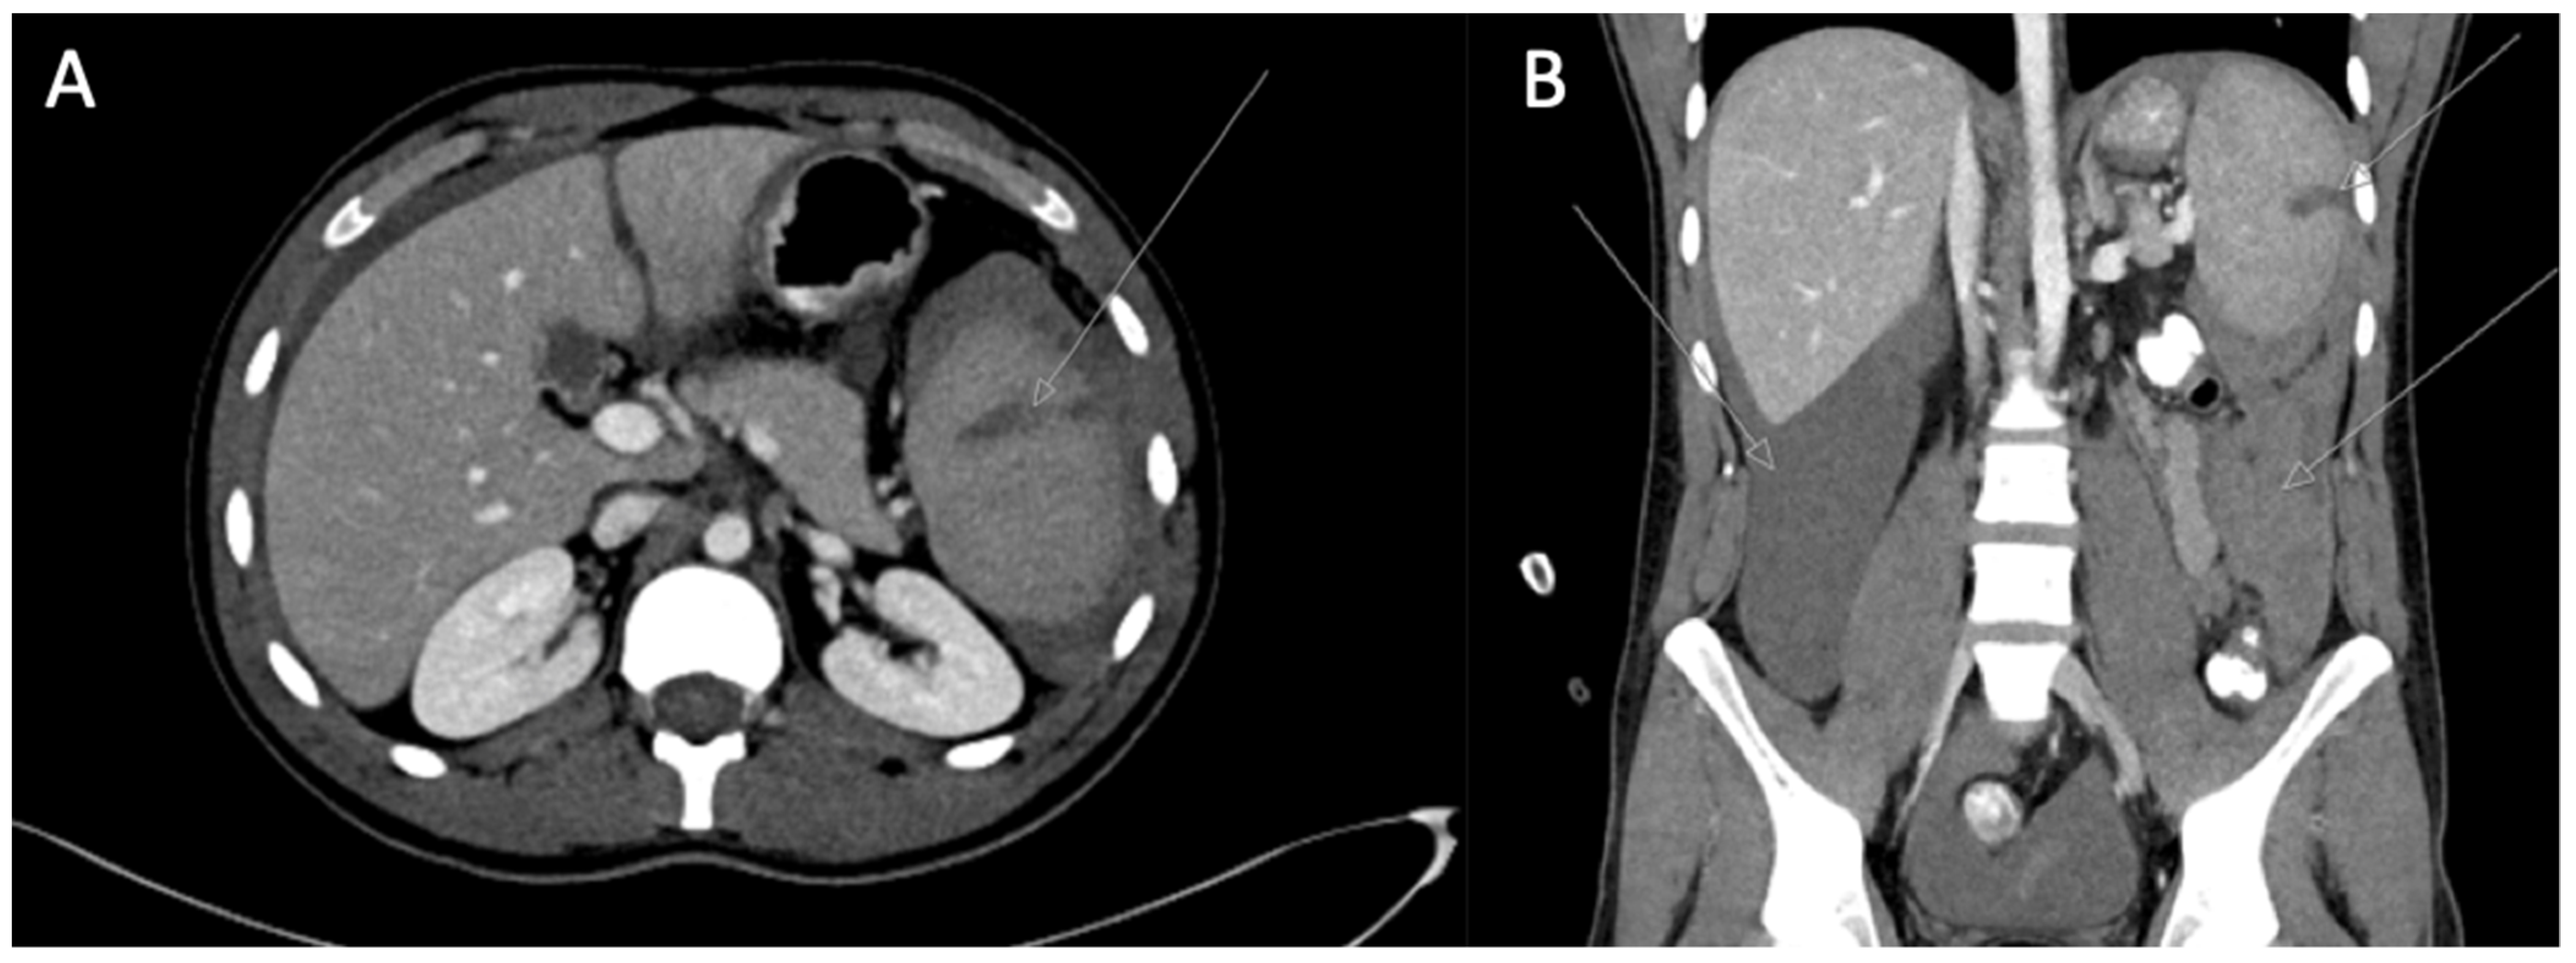

Later on, the patient progressively became respiratorily distressed, and 26 h after extubation, he needed invasive respiratory support because of severe hypoxemia. Chest X-ray showed diffuse infiltrations, and bilateral pleural effusions were seen; ARDS was diagnosed. Turbid pleural effusion was drained and diagnosed as transudate according to Light’s criteria. This case is depicted in Figure 2.

Figure 2. Patient chest X-ray. (L) left side of the patient.